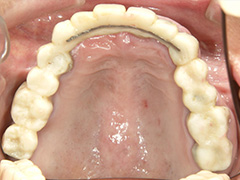

Case.7 コーヌスクローネ義歯骨隆起症例(装着後10年経過)

上顎に入れ歯の床が全くないので発音上の障害はありません。

当院で製作した義歯を外した口腔内

初診時

義歯装着後6年経過時

年齢層 | 60代 女性 |

どんなお悩み | 部分入れ歯が見た感じが悪いのと、発音しずらく、外れやすく困っておられました。そこで、床がない入れ歯を提案させていただきました。かぶせ物を外して、残ってる歯に二重に冠をかぶせて入れ歯をとめる義歯を制作(コーヌスデンチャー) |

治療 期間 | 治療期間は4か月程度 |